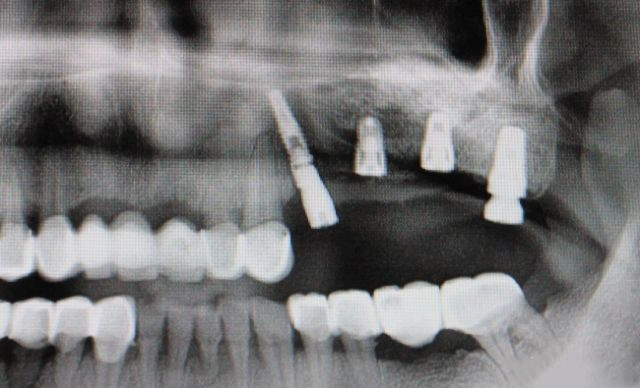

种植体示意图

说一个种植牙价格内幕:种植牙由种植体、基台、牙冠构成,植体费用3000-15000元、基台1500元起、牙冠300-2500元、修复材料1000-3000元、手术及麻醉费用3000-5000元,根据口腔状况及品牌选择,价格还会往上浮动。